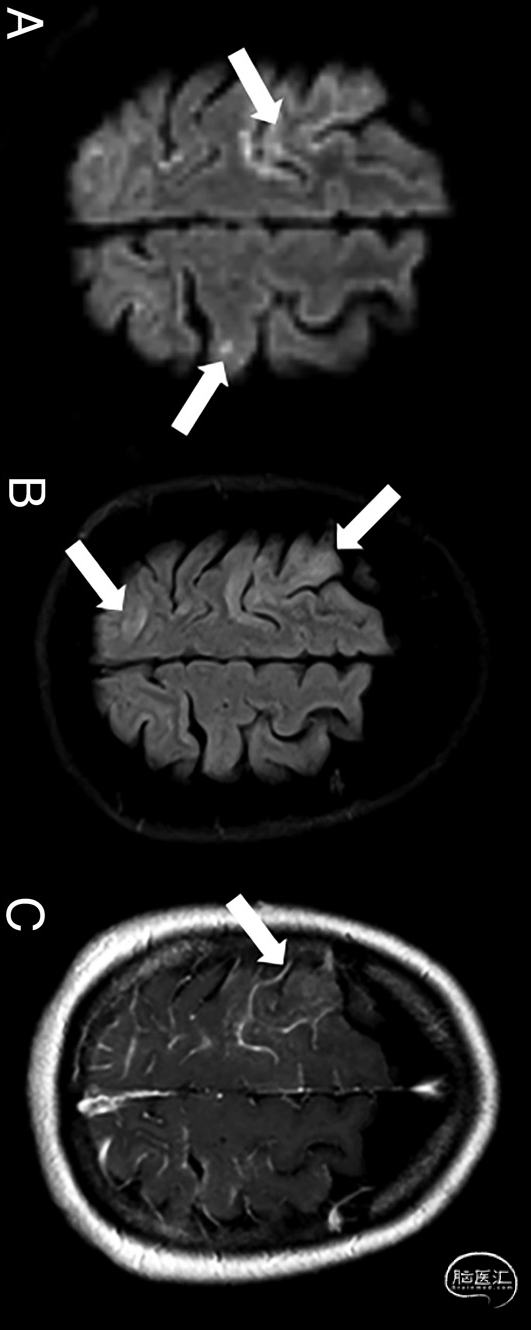

图1. 68岁疑似CAE患者的增强脑MRI。在远端血管床中,呈现细胞毒性水肿(白色箭头,DWI序列,a)和血管源性水肿(白色箭头、T2-FLAIR序列,B)的混合模式,水肿区域附近伴随软脑膜增强(白色箭头;增强后[MultiHance;Bracco Diagnostics]3D gradient-echo T1序列,C):